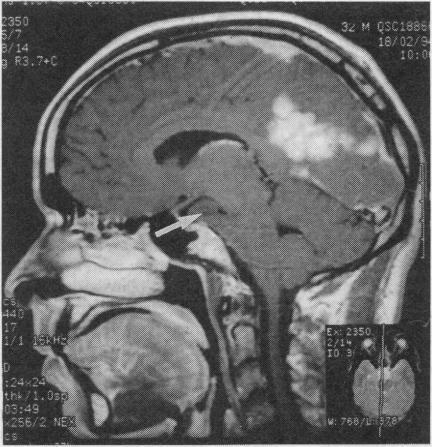

Meningeal granulomas: sarcoidosis or tuberculosis? Differentiation can be difficult.